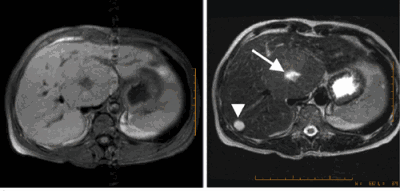

After a year now when I went for a routine scanning it was found that in the liver there is a focal lesion [hyperechoic] with a size of 1.8 cm.

One doctor felt that it would be a haemangioma (a benign tumour composed of dilated blood vessels) but the other one wants to check whether it is a metastatic one.

They want me to do an MRI scan with contrast.